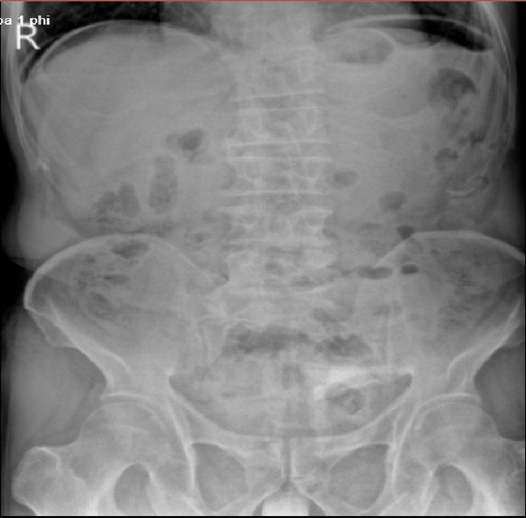

•Kết quả X-quang bụng đứng: Hình ảnh liềm hơi dưới hoành hai bên.